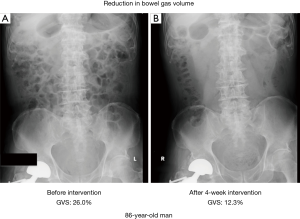

There were over 1.34 million patients suffering from cerebrovascular diseases in 2008 reported by Ministry of Health, Labour and Welfare in Japan. Constipation is one of the complications seen in poststroke patients (10). Japanese medicine Daikenchuto (DKT) improved chronic constipation of poststroke patients. Poststroke patients with functional constipation, assessed by the Rome III criteria, from 6 hospitals were recruited in a study on the effects of the traditional Japanese medicine Daikenchuto (DKT) on constipation. The total score on the Constipation Scoring System (CSS) improved significantly by DKT (Figure 8). The Gas volume score was also significantly reduced in the DKT group compared to the control (Figure 9, P=0.03) (11).